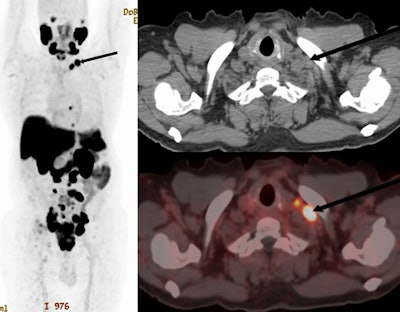

F-18 PSMA-1007 PET/CT of a 70 year old with newly diagnosed prostate cancer: PSA 770 ng/ml; Gleason 5 + 5; International Society of Urological Pathology grade 5. The maximum intensity projection images, CT, and fused images show PSMA ligand-avid prostate primary with pelvic, retroperitoneal, and mediastinal nodal spread. Additionally, he had left supraclavicular nodal metastasis (arrows). Image and caption available for republishing under Creative Commons license (CC BY 4.0 DEED, Attribution 4.0 International) and courtesy of EJNMMI Reports.

According to the findings, the prevalence of SC nodal metastasis in the cohort was 7.9% (n = 19/240). A majority of those with SC nodal metastasis, 84% (n = 16/19) also had associated skeletal metastasis and one patient with SC nodal disease had associated visceral metastasis in the lungs, the group added.